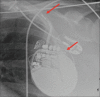

Twiddler's syndrome refers to malfunction of pacemaker or implantable cardioverter-defibrillator (ICD) resulting from deliberate or unintentional twisting of pulse generator in device pocket, resulting in lead dislodgment. We report a case of a 65-year-old woman with multiple ICD shocks and antitachycardia pacing events on device interrogation, while she was unaware of the ICD discharges. Twiddler's syndrome is rare and mostly occurs in obese or elderly because of loose subcutaneous tissue allowing pulse generator to rotate in its pocket. It can be prevented by patient education against hand manipulating the generator. Smaller device pocket or suturing generator to fascia can also prevent future episodes.